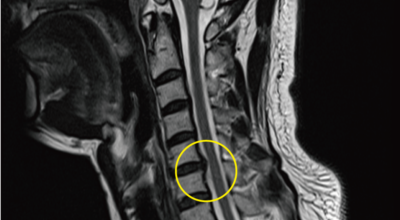

목디스크 증상이 나타날때 빨리 발견하여 비수술 치료를 받고 꾸준히 관리하는 것이 베스트이죠. 목디스크 환자 중 수술을 진행하는 환자는 2% 미만으로 현저히 적다고 해요. 수술을 진행하는 경우는 감각이 느껴지지 않는 마미증후군이나, 한쪽 다리가 눈에 띌 정도로 야윈 경우에만 진행하므로 올바른 자세 교정만으로도 충분히 호전될 수 있는 질병이죠. 목에 연관된 검사는 MRI나 CT를 이용해요. 그러나 전자의 경우 비용이 굉장히 비싸기 때문에 디스크 증세가 확실하다고 생각될 경우에만 선택적으로 하고 의무적으로 하는 건 아니니까 비용에 대해선 부담을 가지지 마시길 바래요.

목디스크 증상으로 인해 3개월 이상 약물이나 물리치료를 해도 효과가 없을 경우 수술을 고려해야 해요. 통증이 심해서 일상생활에 지장이 있거나, 신경증상이 악화되고 근력도 함께 줄어들 때와 큰 디스크가 탈출해 중추신경인 척수를 압박해 척수증이 발생하는 경우에도 수술을 고려할 수 있어요.